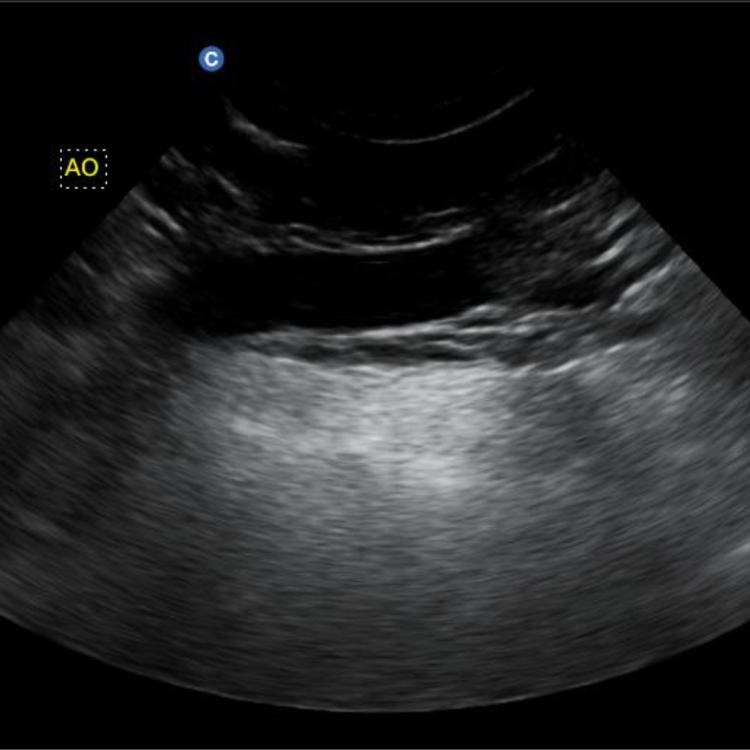

การตรวจอัลตราซาวด์ (Ultrasound) เป็นการตรวจโดยใช้คลื่นความถี่สูงเกินระดับที่หูของคนเราจะได้ยิน การตรวจนี้ค่อนข้างเป็นที่นิยมและใช้กันอย่างกว้างขวาง

สามารถตรวจอวัยวะภายในได้หลายอวัยวะ เช่น หัวใจ หรือ ที่เรียกว่า เอคโคหัวใจ(Echocardiogram) รวมถึงดูอวัยวะในช่องท้องต่างๆ ตับ ม้าม ไต ถุงน้ำดี มดลูก กระเพาะปัสสาวะ รวมไปถึงการดูตัวอ่อนในครรภ์อีกด้วย